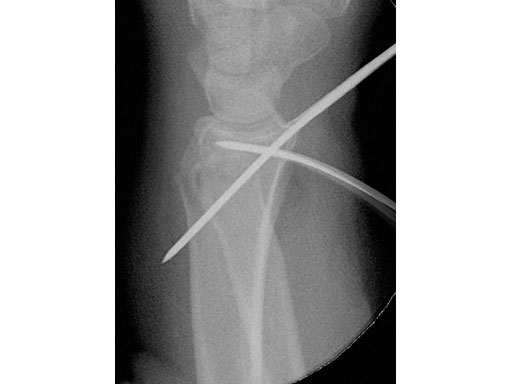

22-year-old male fell off a horse while playing polo.

Fig 1a-b Preoperative x-rays.

Fig 1 Intraoperative view showing reposition of the radiocarpal joint with the K-wire.